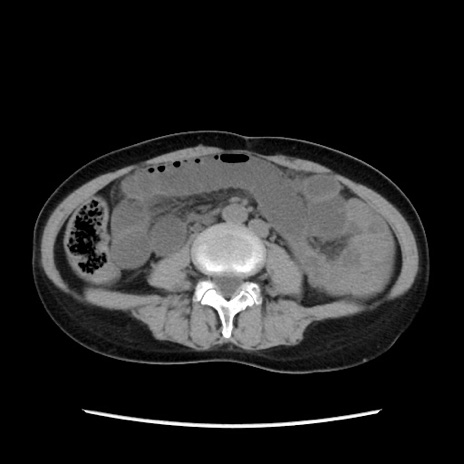

矢状断像

【症例】40歳代 女性

【主訴】上腹部痛、嘔気・嘔吐

【現病歴】約9時間前頃から急に上腹部痛、嘔気、嘔吐が出現。改善しないため救急要請。

【既往歴】子宮頚癌(広汎子宮全摘術、放射線療法)、腸閉塞

【身体所見】腹部:平坦、軟、腸雑音亢進、上腹部を中心に腹部全体に圧痛あり。

【データ】WBC 8400、CRP 0.03